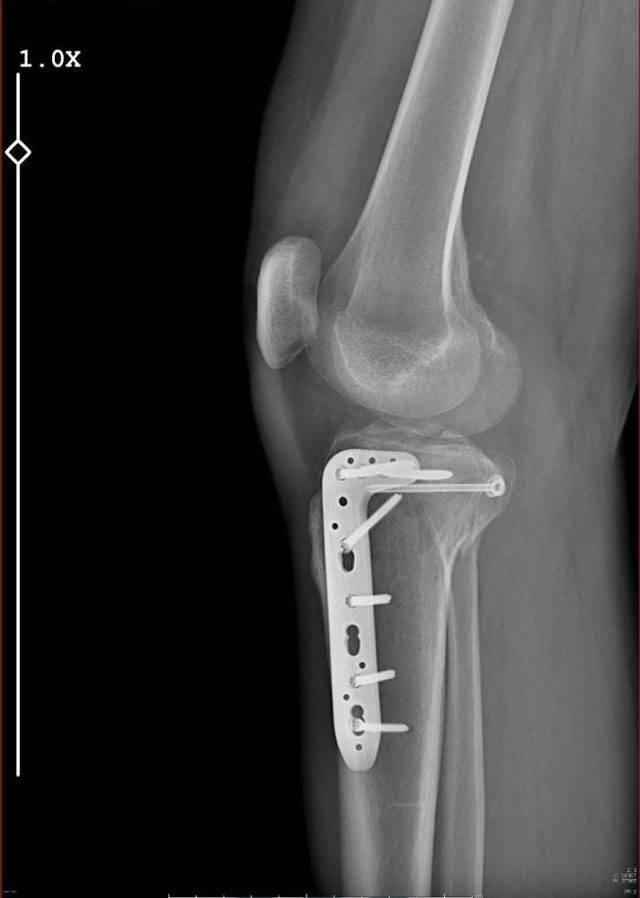

Uzun’a küfürler ederek aracı durdurmasını isteyen H.T.Ü. araçtan inip yanına gelen Fatih Uzun’a saldırmaya başladı. Aldığı darbeler sonucu bacağı iki yerden kırılan avukat geçirdiği ameliyatlar sonucunda 10 gün hastanede kaldı.

Bu olay nedeniyle hastanede 10 gün kaldım. Ciddi bir ameliyat geçirdim, ayaklarımın üstüne basamıyorum. Tedavim yaklaşık 20 hafta sürecek. Yaşanan bu olayda araç içerisinde 5 ve 9 yaşında kızlarım vardı. Çocuklarım benim sakat kalacağımdan korkuyorlar” dedi.